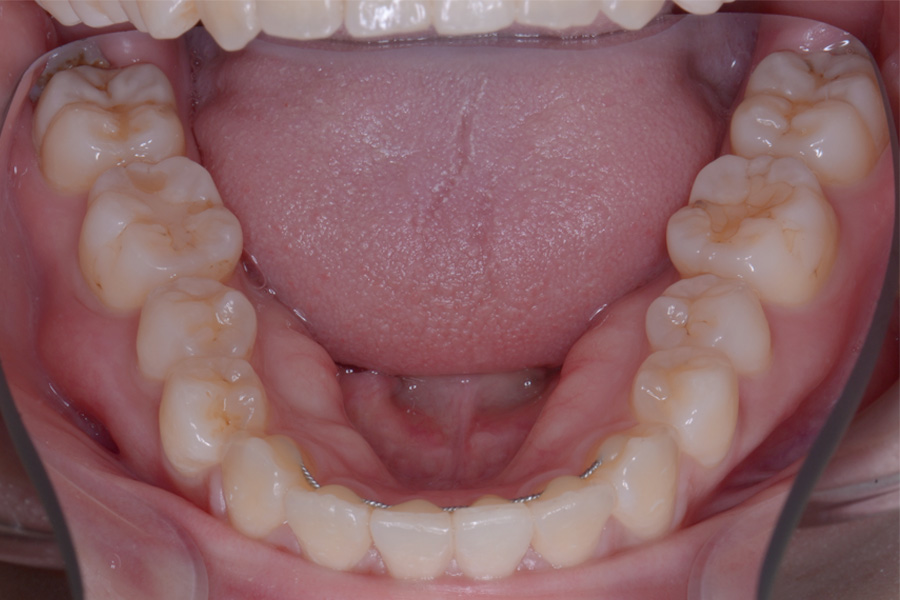

【20代女性】

飛び出ている2本の歯を引っ込めて

下の捻じれている歯を並べたい

治療前

主訴 飛び出ている2本の歯を引っ込めて下の捻じれている歯を並べたい

治療内容 ハーフリンガル矯正(上顎裏側・下顎表側矯正)